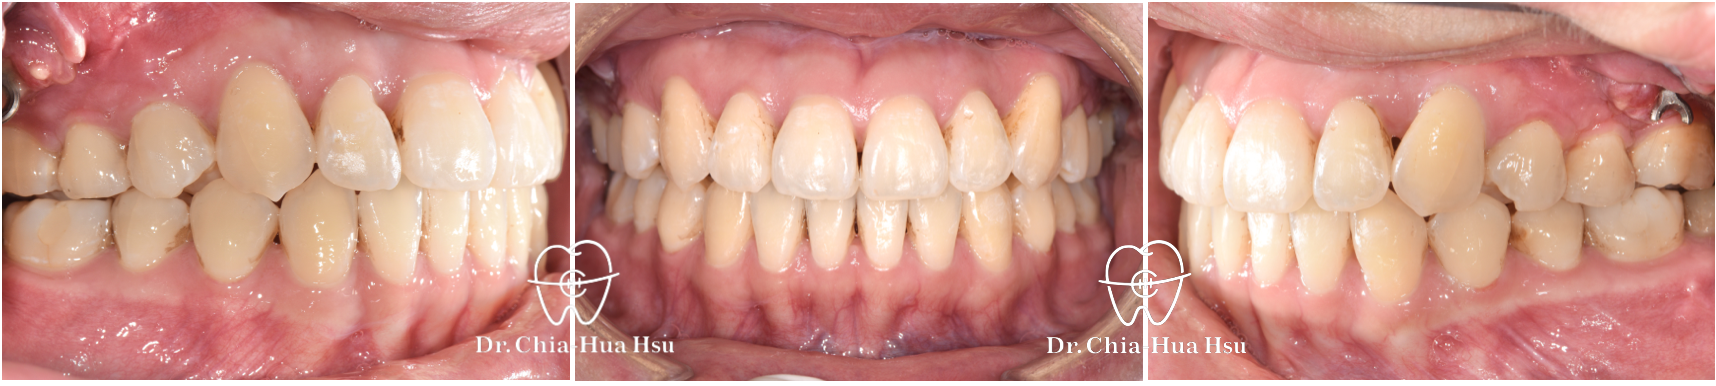

治療前

治療後